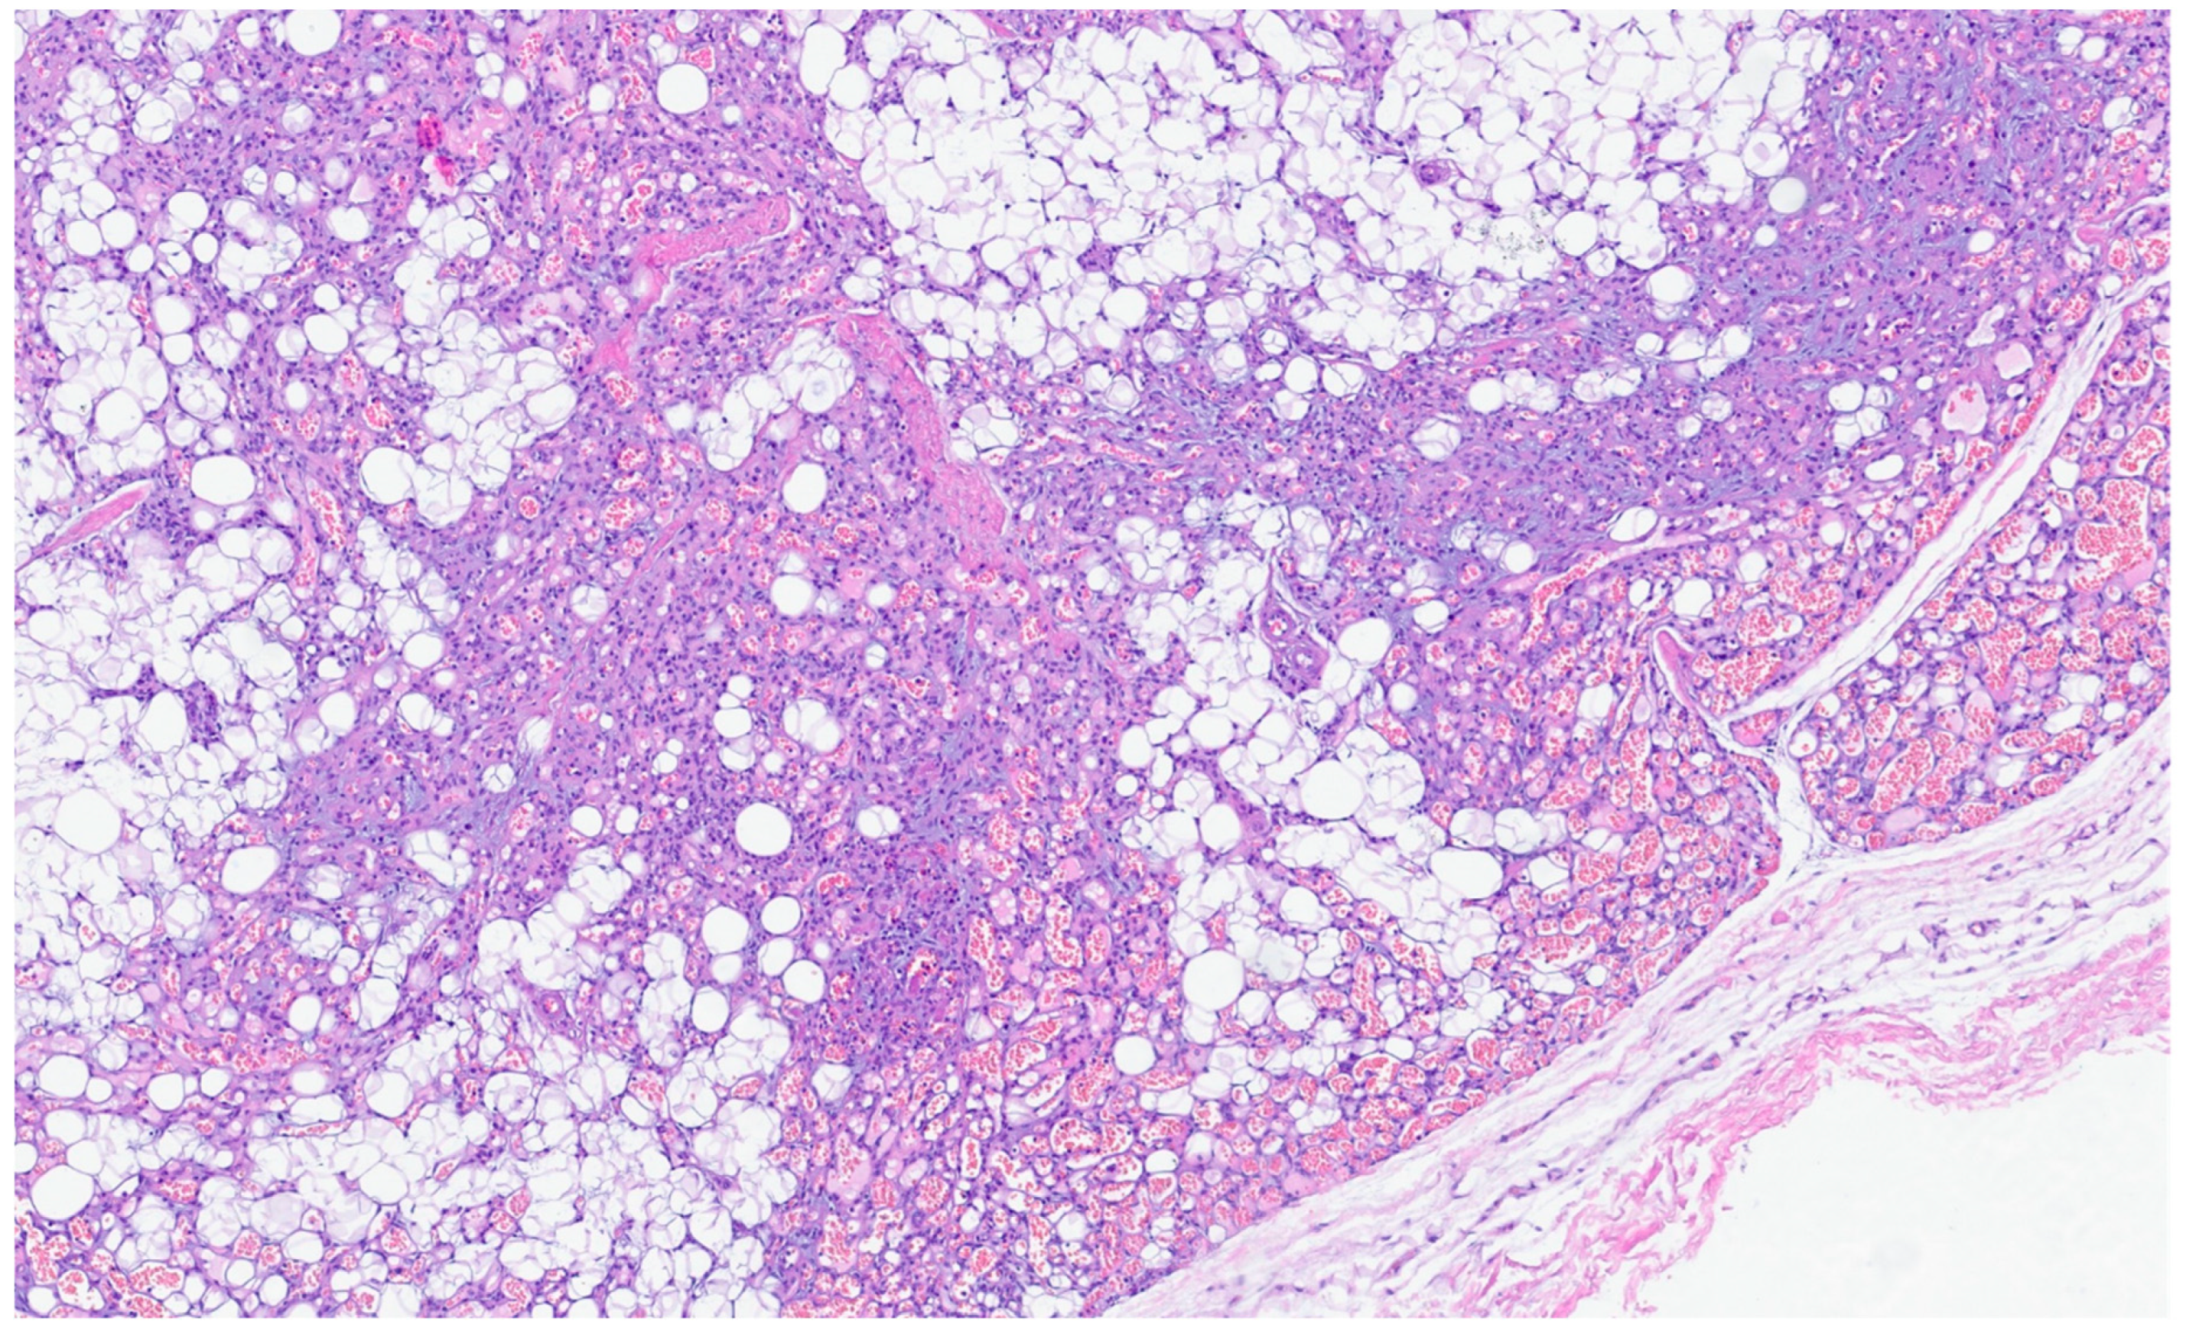

| Lipoma | Adults | Anywhere in the GI tract | Asymptomatic; some cases in the ileocecal valve with obstruction | Mature adipose tissue | S100, Rb1 is retaned, CD34 is negative |

| PEComa | Rare | Colon and small intestine | Symptoms are not specific | Nested, trabecular, and alveolar architecture, surrounded by a delicate vasculature; the cells are usually epithelioid with round to oval nuclei with a granular eosinophilic cytoplasm, but a minority of spindle cells can be seen | α-SMA, desmin, HMB-45 Melan-A, MiTF |